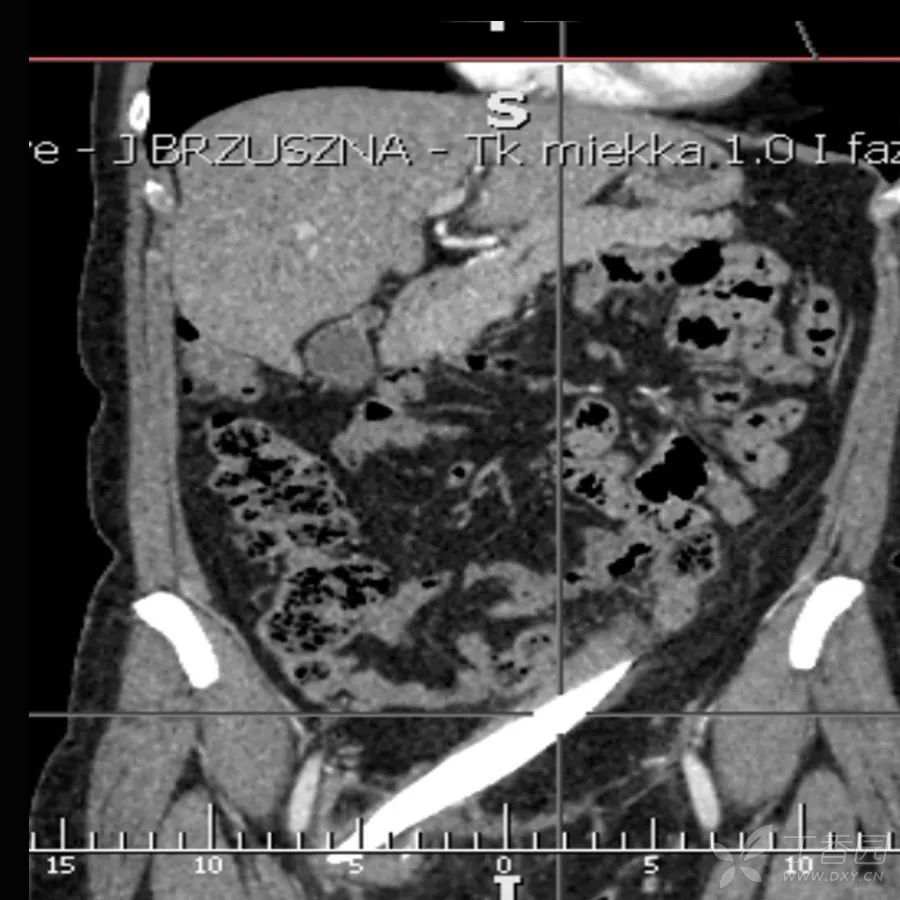

腹腔CT

在腹腔内发现一块19厘米长的玻璃碎片,在盆腔内呈环状。